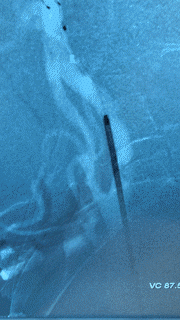

- Carotid Endarterectomy: This procedure is used to surgically open the carotid artery in the neck, remove the plaque, and re-construct the artery to improve blood flow and prevent future strokes (Figure 2). This is considered the standard surgical treatment for carotid stenosis needing operative treatment. Among patients with greater than 70% blockage, performing carotid endarterectomy surgery reduces the rate of stroke over the next two years by 17% and the risk of major stroke or death by 10.6% compared to medical management.